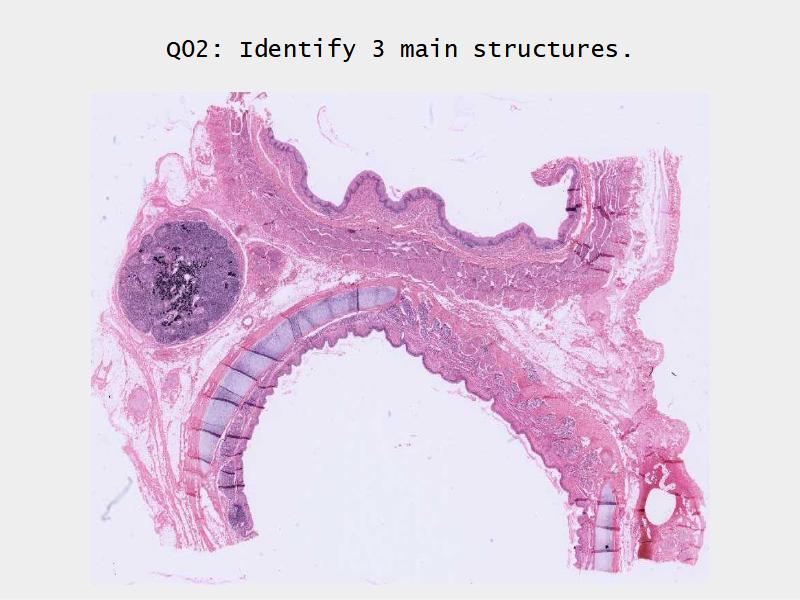

Slides: Respiratory System

- Slide 73: Trachea

Trachea